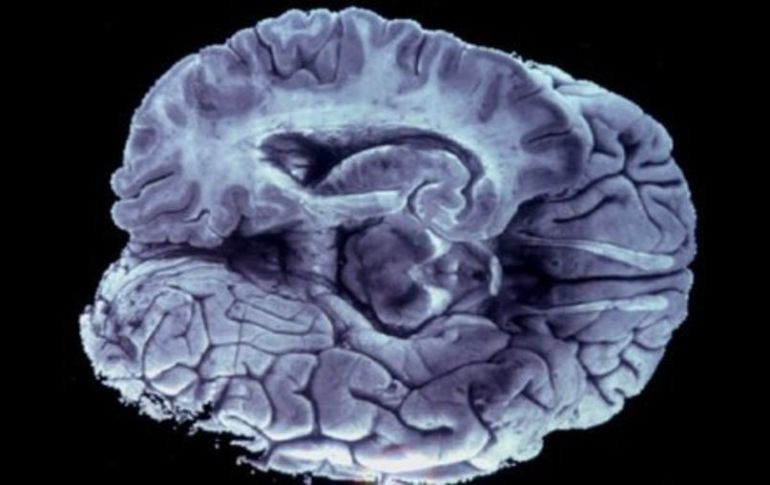

Tecnología | Médicos europeos establecen un nuevo método de investigación Estudian el Alzheimer con tecnología espacial Médicos europeos establecen un nuevo método de investigación con el software AlzTools Por: EL INFORMADOR 7 de julio de 2013 - 19:01 hs Hasta ahora los doctores estudiaban las imágenes cerebrales ''a simple vista''. ARCHIVO / CIUDAD DE MÉXICO (07/JUL/2013).- Gracias a la tecnología espacial, ahora los médicos han podido establecer un nuevo método para estudiar el Alzheimer. De acuerdo con la European Space Agency (ESA), esta innovación se origina en el software utilizado para procesar las imágenes tomadas del espacio. “Cuando trabajas con una imagen por satélite, necesitas rutinas especiales para extraer información de una parte de la imagen, que puede ser un campo o una cosecha (…) el análisis de las imágenes por satélite se puede comparar con lo que tienen que hacer los médicos para comprender el resultado de los escáneres cerebrales, como las IRMs (de resonancia magnética)”, explicó a ESA Carlos Fernández de la Peña, uno de los ingenieros informáticos de la empresa española Elecnor Deimos. Pero, ¿de qué forma la tecnología ayudará a los enfermos de Alzheimer? Pues Deimos trabajó en colaboración con los especialistas de la Universidad Politécnica de Madrid para desarrollar AlzTools 3D Slicer, herramienta que ya se emplea en la investigación de la enfermedad en la Facultad de Medicina de la Universidad de Castilla la Mancha en Albacete, España. AlzTools se utiliza para analizar los datos tomados por un escáner cerebral, en vez de un satélite de observación de la Tierra. Analizan zonas del cerebro como el hipocampo, cuya atrofia está relacionada con el Alzheimer. “Trabajamos muy ligados a la industria española y a Elecnor Deimos en particular a través de ProEspacio, la Asociación Española de Compañías del Sector Espacial, para promover la adaptación de la tecnología espacial en otros sectores industriales”, explicó Richard Seddon, de Tecnalia, el agente tecnológico para España del Programa de Transferencia Tecnológica de la ESA. Sin embargo, no resulta tan fácil, ya sea en el espacio o en la Faculta de Medicina, se tiene que “encontrar sentido a una tonelada de datos”. Ricardo Insausti Serrano, médico e investigador, se encargó de explicar a los ingenieros informáticos el funcionamiento del cerebro humano. “Miraba las imágenes y les explicaba qué función cumple cada parte”, dijo. Gracias a su enseñanza, ayudó a los ingenieros a identificar qué datos podrían ser útiles para un médico que esté buscando indicios de la enfermedad. “Esta técnica nos permite cuantificar una atrofia del lóbulo temporal. Si sabes dónde mirar, puedes estimar cuánto volumen se ha perdido”, expresó. Según ESA, la herramienta es totalmente revolucionaria, pues hasta ahora los doctores estudiaban las imágenes cerebrales “a simple vista”, actualmente es posible desarrollar un método más sencillo y fiable para diagnosticar el Alzheimer. “Es como en el caso del cáncer de mama: las mamografías han supuesto un gran avance para la población”, expresó Serrano. Sinembargo.mx Temas Ciencia médica La Agencia espacial Europea Alzheimer Lee También NASA confirma si el cometa 31/ATLAS amenaza la vida en la Tierra o no Detienen a cuatro jóvenes armados con fusiles automáticos en Sinaloa Conmociones cerebrales, la cuarta lesión más frecuente en partidos de la Conmebol Estudio chino revela una mutación que eleva riesgo de alzhéimer Recibe las últimas noticias en tu e-mail Todo lo que necesitas saber para comenzar tu día Registrarse implica aceptar los Términos y Condiciones